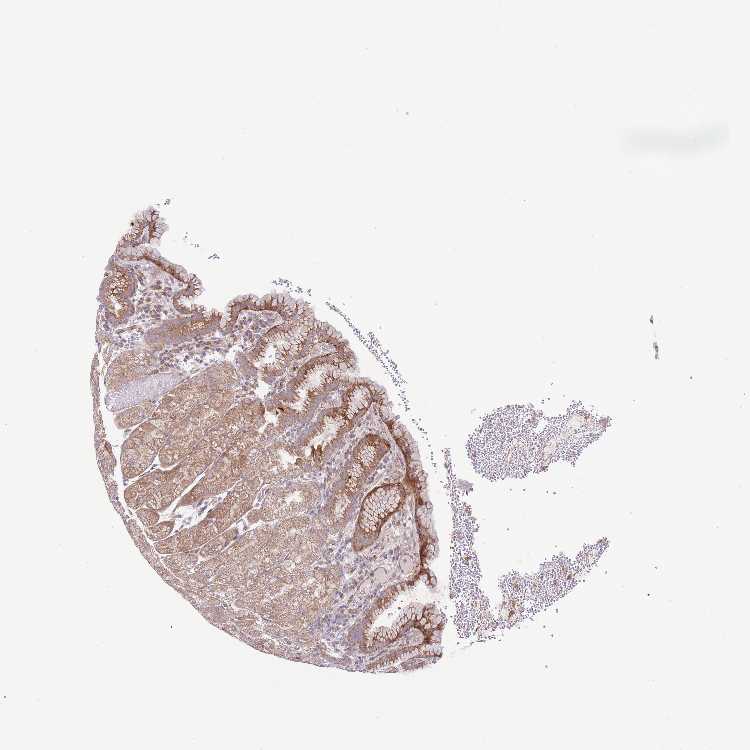

STOMACH 1 - Antibody stainingi

Antibody staining in the annotated cell types in the current human tissue is reported as not detected, low, medium, or high, based on conventional immunohistochemistry profiling in selected tissues. This score is based on the combination of the staining intensity and fraction of stained cells.

Each image is clickable and will lead to virtual microscopy that enables deeper exploration of all samples and also displays staining intensity scores, fraction scores and subcellular localization as well as patient and tissue information for each sample.

Antibody HPA048712

Glandular cells Medium